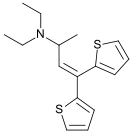

The pharmacodynamic response to an opioid depends upon the receptor to which it binds, its affinity for that receptor, and whether the opioid is an agonist or an antagonist. For example, the supraspinal analgesic properties of the opioid agonist morphine are mediated by activation of the μ1 receptor; respiratory depression and physical dependence by the μ2 receptor; and sedation and spinal analgesia by the κ receptor. Each group of opioid receptors elicits a distinct set of neurological responses, with the receptor subtypes (such as μ1 and μ2 for example) providing even more [measurably] specific responses. Unique to each opioid is its distinct binding affinity to the various classes of opioid receptors (e.g. the μ, κ, and δ opioid receptors are activated at different magnitudes according to the specific receptor binding affinities of the opioid). For example, the opiate alkaloid morphine exhibits high-affinity binding to the μ-opioid receptor, while ketazocine exhibits high affinity to ĸ receptors. It is this combinatorial mechanism that allows for such a wide class of opioids and molecular designs to exist, each with its own unique effect profile. Their individual molecular structure is also responsible for their different duration of action, whereby metabolic breakdown (such as N-dealkylation) is responsible for opioid metabolism.

There are a number of broad classes of opioids:[260]

- Fully synthetic opioids: such as fentanyl, pethidine, levorphanol, methadone, tramadol, tapentadol, and dextropropoxyphene;